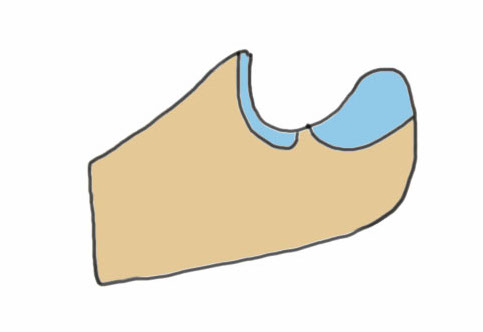

Anatomy

Proximal articular portion of the ulna

- greater sigmoid notch articulates with trochlea

- has a central bare area

- flexion / extension